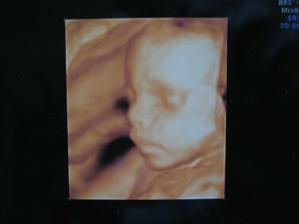

Jmenuji se Tadeášek,narodil jsem se o 5 týdnů dřív,17.6.2009 v olomoucké porodnici,naměřili mi 46cm a vážil jsem 2750g,mám se čile k světu a jsem hodný andílek,maminku ani tatínka moc nezlobím.

V albíčku mám fotečky ještě od mamky z bříška a taky můj provizorní domeček týden po týdnu.No a hlavně moje první dny,tak se koukněte :o)